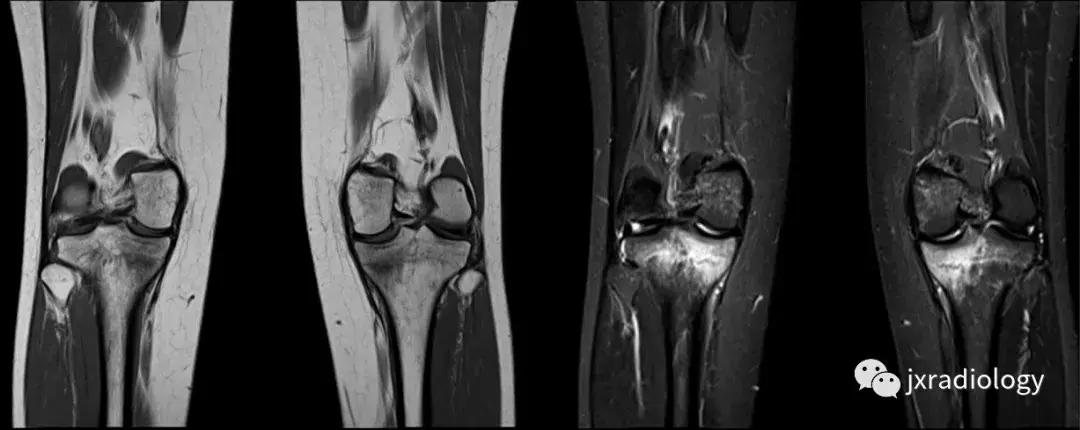

图3:应力(疲劳)骨折:女,25岁,最近在没有适当热身的情况下在健身房参与剧烈运动的冠状位T1WI和STIR图像。 她主诉出现双侧内侧胫骨疼痛。 在双侧胫骨中,内侧近端应力性骨折是明显的。

图4:SIF(软骨下不全性骨折):在过去,每当在股骨内侧髁上观察到这种软骨下病变时,它就被标记为膝关节自发性骨坏死(SONK)。 现在它被认为是一个不全性骨折。这些不全性骨折通常发生在股骨内侧髁和股骨头,并存在于老年人中(它们与骨质疏松症和生物力学改变相关,如在不稳定的半月板损伤中。 与其他应力性骨折类似,低信号的骨折线在水敏性序列(a,b:冠状和矢状PDWI-FS)上被高信号的骨髓水肿包围。